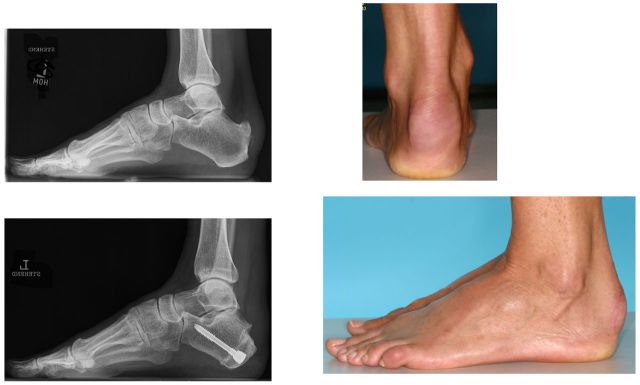

Bei der Calcaneusosteotomie wird meistens über einen aussenseitig am Fersenbein gesetzten 3 cm langen Hautschnitt gearbeitet. Die häufigste Technik ist eine sogenannte Verschiebeosteotomie (sliding Technik). Dabei wird der hintere Anteil des Fersenbeins inklusive des knöchernen Sehnenansatzes der Achillessehne entweder nach innen (medialisierend) oder nach außen verschoben (lateralisierend). Die Fixierung erfolgt mittels Kompressionsschrauben. Diese Art von Operation erfolgt häufig im Rahmen der Korrektur eines erworbenen Plattfußes. Nicht selten sind begleitend noch andere Korrekturen zusätzlich notwendig. Nach der Operation muß für 3-6 Wochen eine teilweise Entlastung vorgenommen werden, um ein Anheilen des Knochens zu ermöglichen.

Seltener ist eine sogenannte zuklappende Osteotomie bei einer ausgeprägten Haglundexostosen-Erkrankung. Dabei wird bei übergroßem dorsalem Fersenbeinhöcker ein ca. 12-15 mm messender Knochenkeil aus dem Fersenbein geschnitten und der gesamte hintere Anteil des Fersenbeins nach „vorne" geklappt und am Fersenbeinkörper verschraubt (Zadek-Osteotomie).